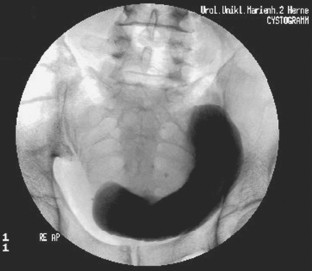

Große Raumforderungen im kleinen Becken können die Harnblase verdrängen und Blasenfunktionsstörungen mit unterschiedlicher Symptomatik hervorrufen. Wir beschreiben den Fall eines 42-jährigen Patienten, der über eine Harnstrahlabschwächung und Restharngefühl bei reduziertem Blasenfüllungsgefühl seit frühester Jugend berichtete und nach zahlreichen konservativen Therapieversuchen neurourologisch evaluiert werden sollte. Bei der Diagnostik zeigte sich eine große zystische, die Blase verdrängende Raumforderung, die einer Retentionsmukozele (bei Zustand nach konnataler Analatresie und chirurgischer Versorgung) entsprach und operativ entfernt wurde.

Large pelvic masses can displace the urinary bladder and cause bladder dysfunction with various symptoms. We report the case of a 42-year-old man who described a feeling of reduced urinary stream and bladder filling and residual urine since his youth. After various unsuccessful conservative treatments, the patient was evaluated by our neurourologic department. The diagnostic workup revealed a large cystic mass that displaced the urinary bladder. Histopathological examination showed a retention mucocele (the patient had been surgically treated for connatal anal atresia). The lesion was surgically excised.

Abb. 1